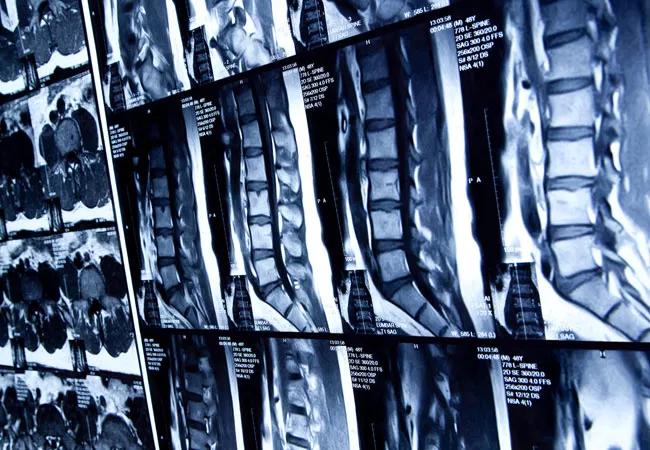

Promising Early Results from High-Frequency Spinal Cord Stimulation Study

Most patients who received stimulation reported a reduction of pain between 50-80%

An ongoing study of high-frequency spinal cord stimulation for painful peripheral diabetic neuropathy is producing promising early results. This research may provide an effective alternative to the unpleasant side effects commonly associated with the limited treatment options currently in use.

The multi-center, randomized trial sponsored by Nevro Corporation compares high-frequency (10kHz) therapy with conventional treatment for patients with refractory diabetic neuropathy. High-frequency therapy involves the application of short-duration (30μs), low amplitude (1-5 mA) pulses to the spinal cord, using small electrodes implanted in the epidural space.